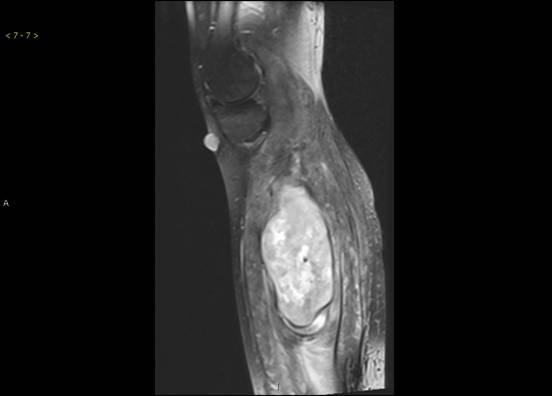

专科检查骨科情况右小腿后侧可触及8cm*3cm大小实性肿物,质中,可移动,边界不清,压痛。局部皮肤无溃破糜烂,皮温正常。左下肢感觉无异常,肌力、肌张力正常。 MRI:左侧小腿巨大软组织肿块,考虑肿瘤性病变,低度恶性可能性大,伴左侧腓骨受压变形。建议活检。

诊断:(左小腿肌肉肿瘤)肉瘤 治疗:在全麻下行 左小腿肿瘤切除术,术后给予对症治疗及相应的理疗及功能锻炼,患者症状明显缓解,切口愈合好。术后病理示:(左小腿肌肉肿瘤)肉瘤,恶性外周神经鞘瘤,低度恶性。